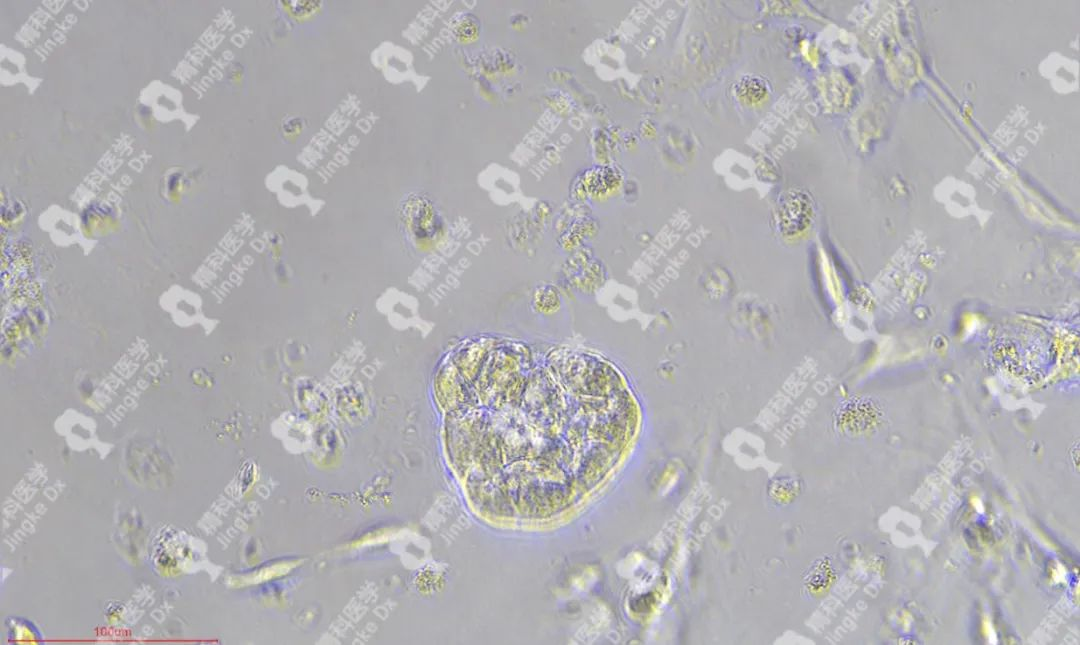

精科類器官培養(yǎng)相關(guān)服務(wù) 精科醫(yī)學(xué)作為類器官技術(shù)轉(zhuǎn)化先行者致力于推動類器官技術(shù)的轉(zhuǎn)化與應(yīng)用,對基于類器官培養(yǎng)擁有成熟的技術(shù)與經(jīng)驗。精科類器官團隊技術(shù)深耕十余年,擁有國內(nèi)頂級的類器官團隊,超微量建模技術(shù)成功率高達95%以上,有成功建模30+種腫瘤的經(jīng)驗(包括上述子宮內(nèi)膜癌、宮頸癌和卵巢癌)??梢蕴峁┌惼鞴俳Ec保存(建模、凍存、傳代)、類器官檢測(類器官H&E染色、免疫組化、藥物敏感度篩選)等多種類器官相關(guān)服務(wù)。檢測服務(wù)最快可在十個工作日內(nèi)完成,更好為患者爭取治療時間。 ★ PIC.01 精科卵巢癌類器官圖像 ★ PIC.02 精科宮頸癌類器官圖像 ★ PIC.03 精科子宮內(nèi)膜癌類器官圖像